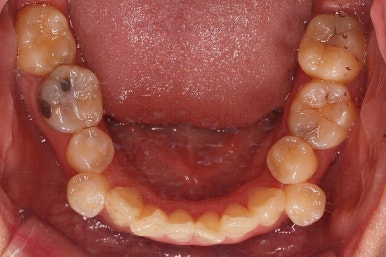

아랫니는 많이 삐뚤긴 했지만 옆라인, 턱의 크기 등 모든 걸 종합적으로 판단해 비발치로 진행하기로 했습니다.

공간을 줄여나가고 순차적으로 충치치료도 마무리 해갑니다.

교합이라던가 부족한 부분을 좀 더 마무리하고요.

마무리 못한 어금니 치료와 앞니 심미보철을 마무리 합니다.